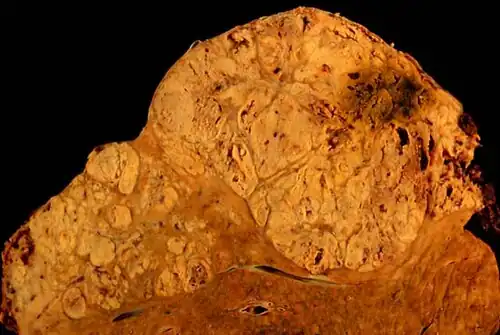

Цирроз печени, приведший к гепатоцеллюлярной карциноме (макропрепарат) | |

Цирротичная печень увеличена или уменьшена в размерах, необычно плотная, бугристая, шероховатая. Десятилетняя смертность от постановки диагноза составляет 34—66 %, в зависимости от причин: алкогольный цирроз имеет худший прогноз, чем связанный с другими причинами. Первое известное описание заболевания было за авторством Гиппократа в 5-м веке до нашей эры[2]. Сам термин «цирроз» был изобретён в 1819 году из-за желтоватого цвета больной печени[3].